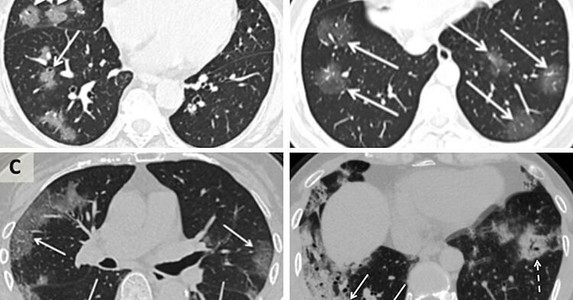

Diễn tiến nCoV xâm nhập phổi Tiến sĩ Shu-Yuan Xiao, giáo sư bệnh học tại Đại học Y khoa Chicago kiêm giám đốc của Trung tâm chẩn đoán bệnh học và phâ...